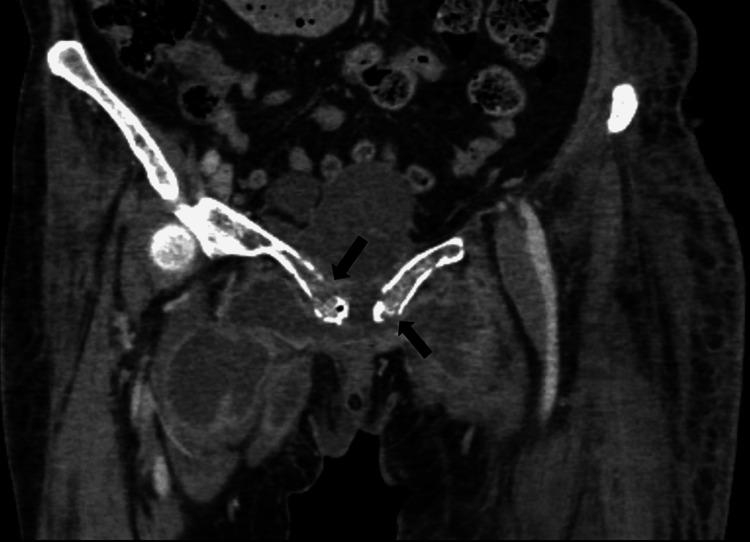

Emphysematous osteomyelitis is an uncommon and fatal disease that can only be confirmed with a contrast-enhanced CT scan showing characteristic features of air locules within the bone. It usually occurs in the setting of existing comorbidities and suppressed immune system resulting in widespread bacteremia which may be mono or poly-microbial. Presented here is a case of this disease caused by an unusual anaerobe affecting the pubic bone. This case emphasizes the importance of early imaging as it is crucial for the diagnosis and can facilitate early aggressive management. Moreover, it highlights the importance of early intravenous antibiotics and surgical intervention, which can be life-saving and result in a better outcome in the future.

气肿性骨髓炎是一种罕见的致命疾病,只有通过增强CT扫描显示骨内有特征性的小气腔才能确诊。它通常发生在存在合并症和免疫系统抑制的情况下,导致广泛的菌血症,可能是单一微生物或多种微生物感染。本文介绍了一例由一种不常见的厌氧菌引起的耻骨气肿性骨髓炎病例。该病例强调了早期影像学检查的重要性,因为它对诊断至关重要,并且有助于早期积极治疗。此外,它突出了早期静脉使用抗生素和手术干预的重要性,这可能挽救生命并在未来带来更好的结果。